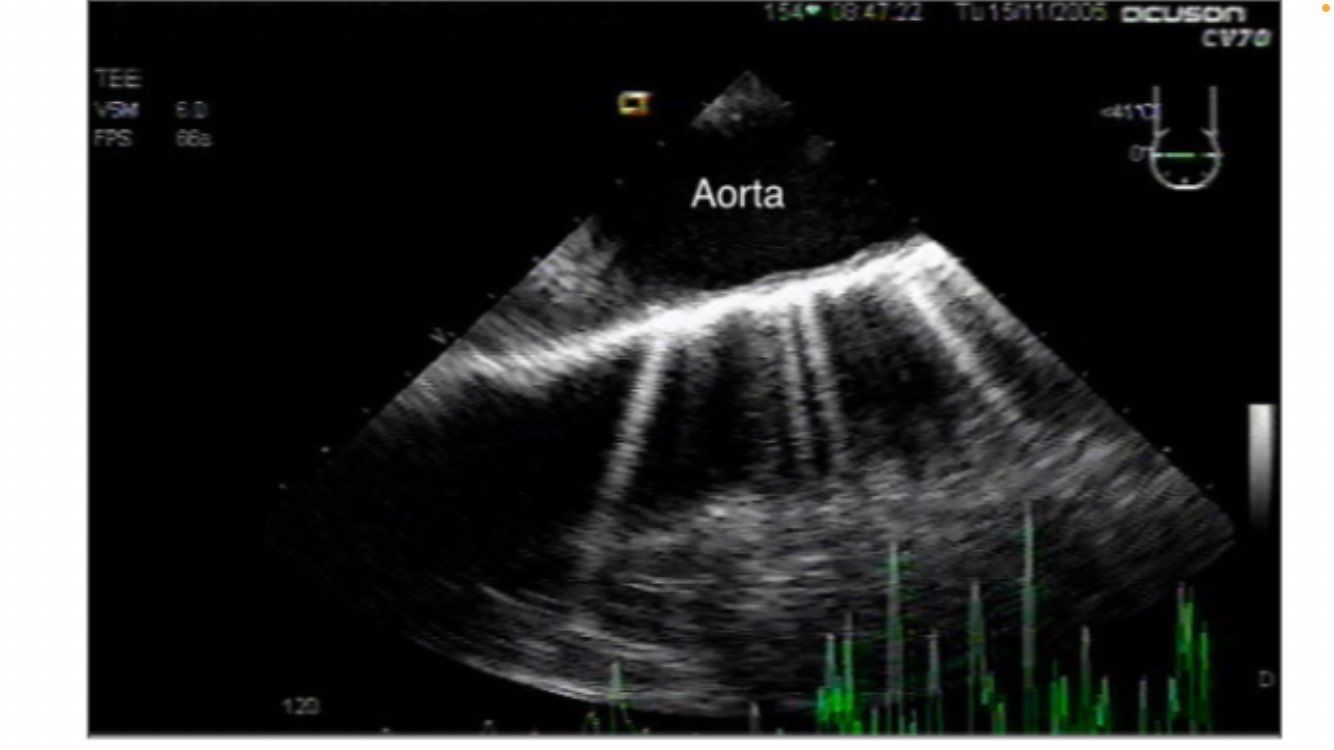

aortic long axis

NO DISSECTION